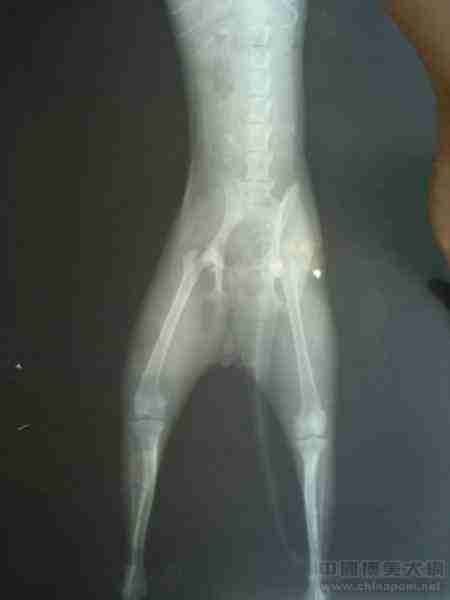

嘉嘉腿部问题的X光片,大家也进来学习下吧

简要说明下嘉嘉的犯病特征:走路提右后腿,跑步时双后腿同时着地成兔子跳,活动量减少,上楼梯困难,睡醒后后腿无力,跟玩伴玩时体力不足,腿发软坐底墒,弹跳力明显下降,发病特点都是偶尔发生的 观察时间:3天 ...

严格来说这个X光片不能用做判断髋关节的病变,第一拍片时没有对嘉嘉使用麻醉,它老乱动,拍成这样我也没有办法了,第二,额。。。这个是仪器还有技术问题了,负责拍片的是2个刚刚毕业的研究生PS。这个偶相当不满!嘉嘉有病我都快要急死了,居然还叫2个实习生来,后来X光片没有出来之前一个已经不在那做的教授帮嘉嘉看了一下,还让2个实习生顺道学习一下,教他们如何判断裸关节膝关节还有宽关节的问题,老教授也说了如果不是骨骼问题就是肌肉韧带软骨的问题,需要好好调理

不知道是因为体位的原因还是什么,看着髋关节总觉得怪怪的,小腿的形状也有点像X形

大夫说小嘉的骨骼没有问题,腿部偶尔出现的坡行有3种可能,肌肉拉伤,韧带拉伤,髋关节软骨挫伤

哎。。。无论是哪一种小嘉都要长时间休养并要一直服用关节药直到坡行,无力等状况消失后才有可能完全康复

髋关节发育不良就是关节窝太浅了,包不住股骨以至股骨脱出关节窝的位置,加上长期的压迫而造成关节损伤和退化,就是所谓的CHD

嘉嘉的X光片髋关节处摆位不是很正,但是看得出来关节窝不浅,能将股股包住了

我看了之后觉得好像是髋关节发育不良

但是我不是专业的骨科医生,对于博美的骨架结构也没有完整的认识,仅供参考